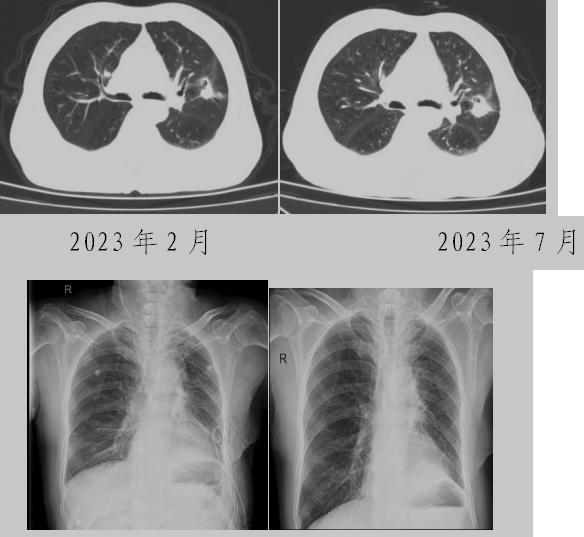

病例一:70多歲的患者王先生于2020年“急性心梗”入院時檢查發(fā)現(xiàn)了肺部結(jié)節(jié),王先生沒有在意,其間未規(guī)范復(fù)查胸部影像學(xué)檢查,于2023年2月份再次發(fā)作心絞痛時,發(fā)現(xiàn)肺結(jié)節(jié)已發(fā)展成直徑約2.5cm實性腫塊,患者在家長期口服“替格瑞洛及腸溶阿司匹林”等抗凝藥物,生活可自理,于冠狀動脈二次植入支架后三個月,收住市二院胸外科,經(jīng)心內(nèi)科、麻醉科等多學(xué)科會診后,由胸外科主任王松陽、副主任醫(yī)師薛飛及科室團隊行“單孔胸腔鏡下左上肺癌根治術(shù)”,術(shù)后結(jié)合快速康復(fù)理念,三天后拔除胸管,一周出院。